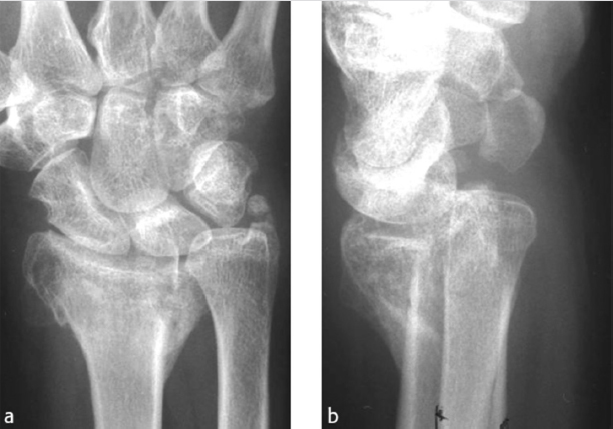

Preoperative planning is essential for intraoperative decision making. Desired angles for correction are determined corresponding to the opposite side (► Fig. 53.4). Using templated X-rays to assess length, osteotomy location, and osteotomy or either printing out X-rays and constructing osteotomies on the paper to determine appropriate cut locations, angles, and center of rotation can be very helpful (► Fig. 53.5). CT-derived threedimensional bone models can allow for preoperative planning.

Two methods for preoperative planning have been described by Nagy and Fernandez on the basis of plain X-ray (► Fig. 53.6). Intra-articular and rotational deformities are difficult to assess on radiographs; the use of three-dimensional imaging and patient-specific guides can help the challenge. 16 , 17